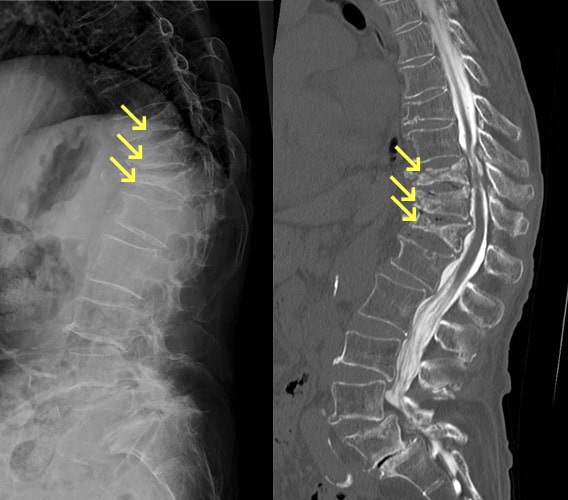

圧迫骨折

骨粗しょう症の方が転倒したり重たいものを持ったりした時に生じることが多いですが、骨粗しょう症が進行すると気づかないうちに骨折をすることもあります(いつの間にか骨折)。痛みのために動くことが困難になり、高齢の方では寝たきりの原因になります。多くの場合は手術をしないで治療を行います。コルセットやギプス固定を行い、安静にします。ただし高齢の方の場合は寝たきり予防のため、痛みに応じて動いていくことが重要です。低侵襲に骨折部へセメントを注入する手術(BKP)や骨折部を安定させる椎体固定術などが行われることもあります。